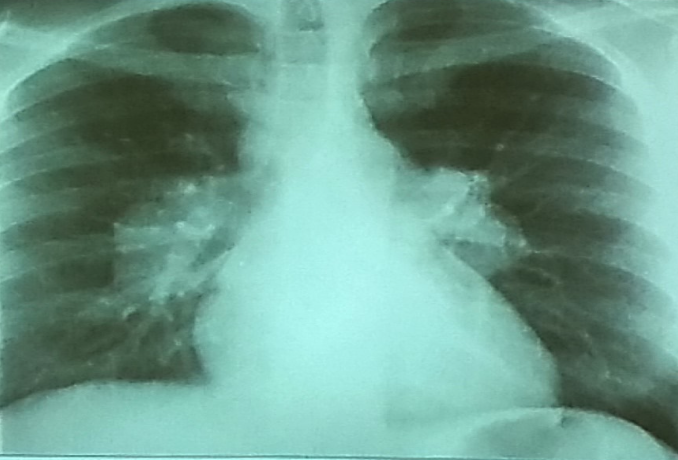

Patient with recurrent attacks of dyspnea and chest tightness after exercise. Clinical diagnosis bronchial asthma. Chest X ray is as follows:

Patient with recurrent attacks of dyspnea and chest tightness after exercise. Clinical diagnosis bronchial asthma. Chest X ray is as follows:

Q1: in this chest x-ray normal or abnormal? Normal.

Q2: on chest auscultation, what added sounds can be heard in asthma? Wheeze.

Q3: Name any drug which can precipitate asthma? NSAIDS, Beta blockers.

Q4: You ordered spirometry for this pt. what will be the expected finding? FEV1 is reduced.

Q5: Name 2 clinical features of severe asthma? Z Can Not complete a sentence in one breath, Tachypnea, cyanosis

Q6: What ttt will you give in moderate to severe asthma? Name any 2. Bronchodilators, corticosteroids.

Patient present with acute chest pain..

Patient present with acute chest pain..

Diagnosis?

- Pneumothorax

What abnormalities do you see?

- lucency of hemithorax

- absent broncho-vascular markings Z

- shifted trachea to the right

Predisposing causes?

- Trauma

- Ruptured alveoli

- Cystic fibrosis

important and prompt steps of management

- (Needle decompression) needle in the second intercostal space midclavicular line to decompress.

- Tube in the 5th intercostal space, anterior axillary line, pushed to the back and upward.